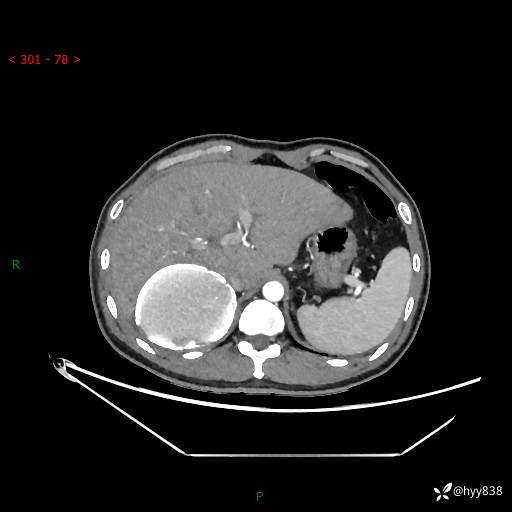

性别:男

年龄:50岁

简要病史:夜尿增多半月,发现肾功能异常1天,超声发现腹膜后占位

腹部CT平扫+增强